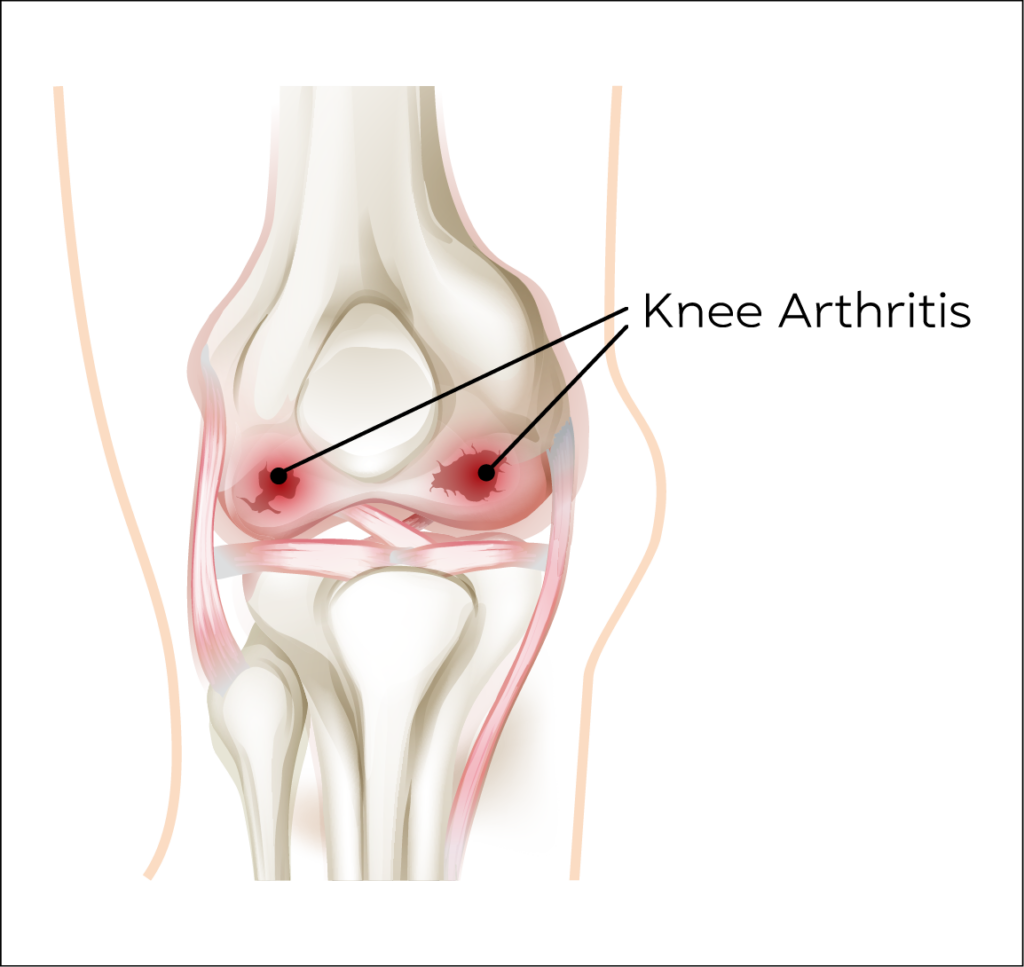

Knee Arthritis

Osteoarthritis is a painful degenerative condition affecting any joint with articular cartilage due to gradual wear and tear of the articular cartilage, which protects the bone ends.

It affects around 18% of the population with 1 in 5 above the age of 45 seeking medical help.

Main symptoms are pain and swelling of the knee with activity and relieved by rest. Early morning stiffness in the initial stages which can progress to constant severe pain, progressing to deformity of the knee joint.

Osteoarthritis cannot be cured by medications, but injections administered into the joint using steroids or Hyaluronic acid do give short and long term relief of symptoms.